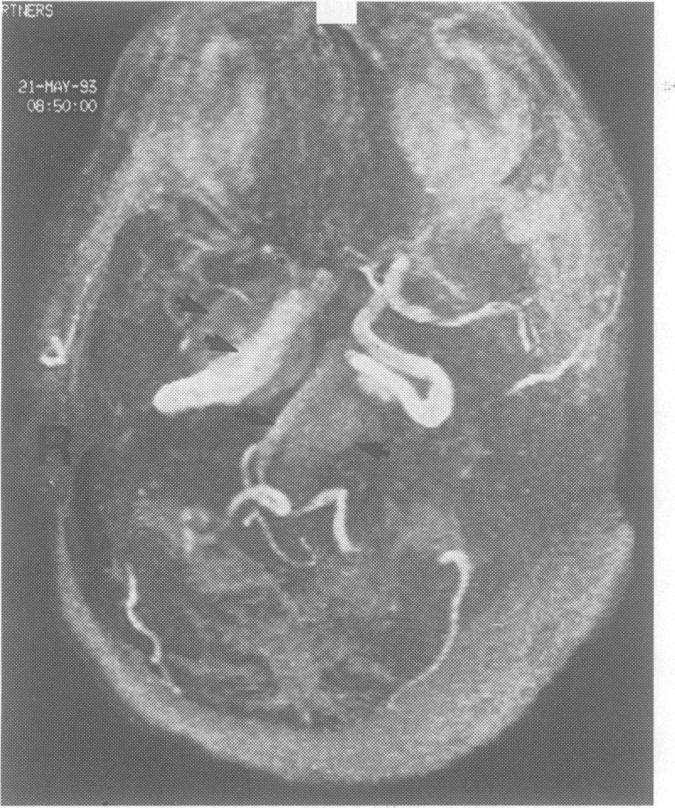

Mills' syndrome: ascending (or descending) progressive hemiplegia: a hemiplegic form of primary lateral sclerosis?

J Neurol Neurosurg Psychiatry. 1994 Oct;57(10):1280-1. doi: 10.1136/jnnp.57.10.1280.